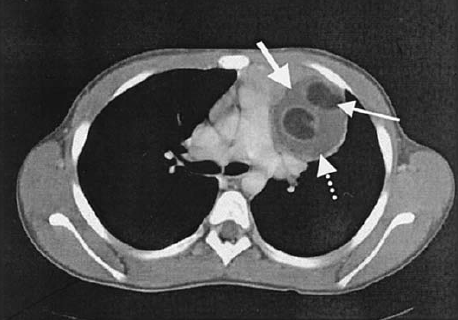

Endoskopiyadan sonra emfizemanın ortaya çıxması, oral kontrastlı rentgendə və ya KT-də kontrast ekstravazasiyası qida borusu perforasiyasını göstərən əlamətlərdir (Şəkil 11).

Şəkil 11. R-qramma. Kontrastın ekstravazasiyası